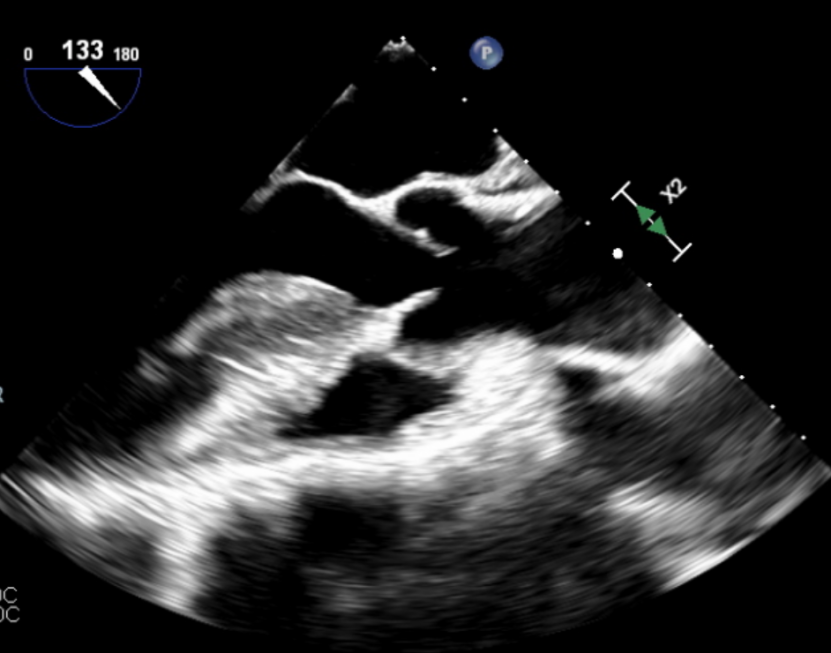

左室长轴切面可见流出道结构良好,短轴切面可见主动脉瓣大量反流。

(流出道结构观察)

(短轴切面观察)

输送器顺利跨瓣,释放外鞘管,开始定位释放,超声评估可见定位件入窦可,后释放内鞘管,打开瓣架,瓣叶活动良好,无瓣周反流,综合考虑瓣膜稳定良好,脱钩释放。

脱钩后输送器回收,瓣膜无位移及形变,确认瓣膜完全脱钩,回撤输送系统,超声再次评估,瓣膜位置及形态良好,无瓣周漏,峰值流速1.18m/s,平均压3mmHg,患者未诉不适,入路缝合后返回病房。